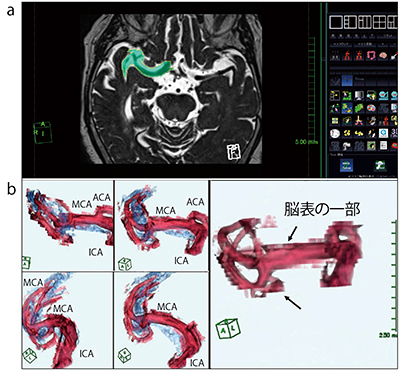

中大脳動脈水平部前後の25枚に対して,マニュアルでスライスごとに領域を選択し,カラーマップやレイヤーを駆使して血管および脳槽を描出したが,見やすい画像の作成に20分程度の時間を要した(図2)。本手法では,領域選択で脳表を領域選択すると血管周囲に脳表が残り,血管走行が見えづらくなる。中大脳動脈周囲の脳槽が狭い非高齢者では領域選択が難しく,脳表の削除作業が必要になり,さらに煩雑な手法であった。

図2 3D-heavy T2WIからの血管抽出方法(従来方法)

3D-heavy T2WIの原画像上で内頸動脈から中大脳動脈をマニュアルで選択し(a),3D構築することでMRAでは確認できない血管分枝が描出できる。しかし,領域選択の際に血管周囲の脳組織を含んでしまうと,血管周囲に脳表の一部が残存し,血管走行が不明瞭になってしまう(b)。髄液腔を青くして血管走行を強調しても,血管分枝がわかりにくい。